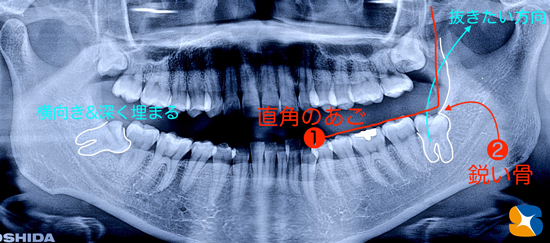

レントゲンの結果、右下:横向きの親知らず(向かって左)が、あご骨の中に深く埋もれている事が分かりました。また、左下:上向きの親知らず(向かって右)もなんとなく難しいのでは?と感じました。

理由は、女性でお口が大きく開かない事にに加え、親知らずが後ろ向きに生えている(通常は前向き)。また、

①あご骨が直角に立ち上げっているのうえに

②歯の周りにあご骨が取り巻いていたため、

骨の切削が難しく削る量も増えていく、といった問題が発生しました。

試行錯誤の結果、ようやく抜歯が終了しました。その結果、歯は、ミツバチのお尻のように膨らんでいたため、あご骨の中からなかなか出てこれませんでした。